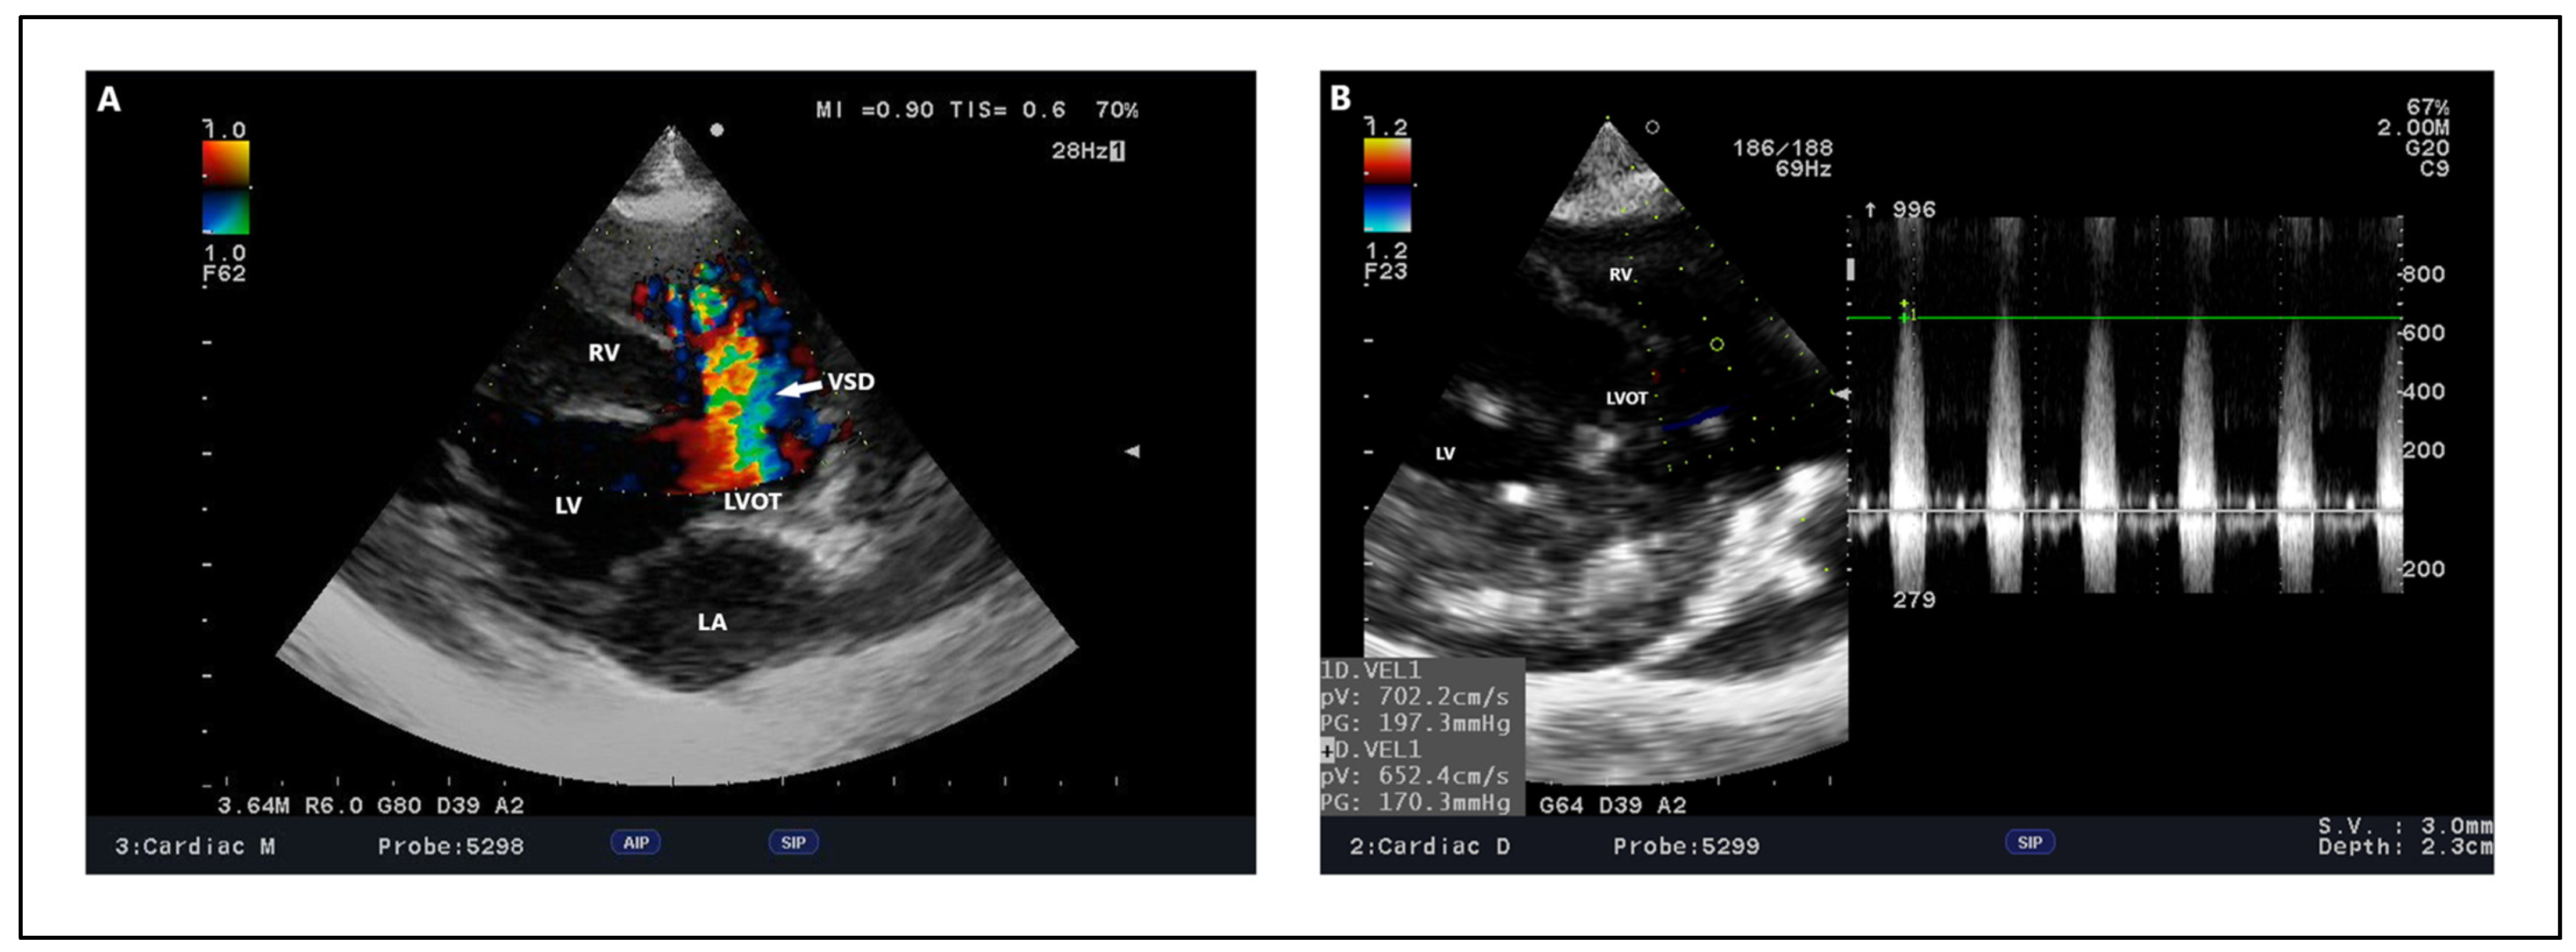

Outflow ventricular septal defect—dog, French Bulldog, four years. (A) Color Doppler, defect in the outflow portion as seen in the right parasternal short right axis view. (B) Color Doppler, defect with an estimated size of 2.9 mm in right parasternal four-chamber view. (C) Spectral Doppler, maximum velocity peak of ventricular septal defect seen from a modified left apical four-chamber view. Ao: aorta. LA: left atrium. LV: left ventricle. RA: right atrium. RV: right ventricle. RVOT: right ventricular outflow tract. VSD: ventricular septal defect.

Figure 9.

Central perimembranous ventricular septal defect, dog, Maltese, six years. (A) Color Doppler, defect in the membranous part of the interventricular septum located under the septal leaflet of the tricuspid valve seen from a modified right parasternal five-chamber view. (B) Spectral Doppler, maximum velocity peak of ventricular septal defect—7.02 m/s in modified right parasternal five-chamber view. LA: left atrium. LV: left ventricle. LVOT: left ventricular outflow tract. RV: right ventricle. VSD: ventricular septal defect.